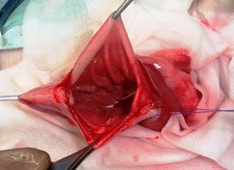

皮下膿瘍

皮下膿瘍とは、噛まれたり、異物が体に刺さったりして、皮下が感染を起こし、膿が皮下に貯まる病気です。

特に外猫ちゃんでは、ケンカをする事が多く、皮下膿瘍になる機会が多いです。

軽度なものは、抗生物質等の内服薬で治りますが、重度になると、皮下組織が壊死を起こし、全身に菌がまわり、敗血症を起こし、重症化することがありますので、外科的治療が必要となります。

下記の症例は、皮下膿瘍から始まり、皮下組織の壊死が広範囲に及んでいたので、外科的治療を行った症例です。

![]() 背部を咬まれ、背中に膿が貯まって、 |

![]() 皮下に膿がたまり、 |

![]() 壊死組織を全て取り除き、 |

![]() ドレーンを皮下に挿入し、 |